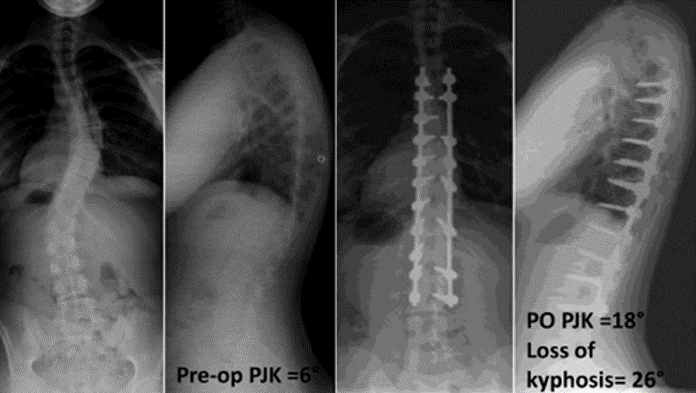

图17 据文献报道,腰椎前凸(LL)过度矫正和SVA基线位置不当,均为增加PJK发生的风险因素

Ø 术后PI-LL不匹配,PI-LL大于10°

图21 术后PI-LL不匹配,大于10°